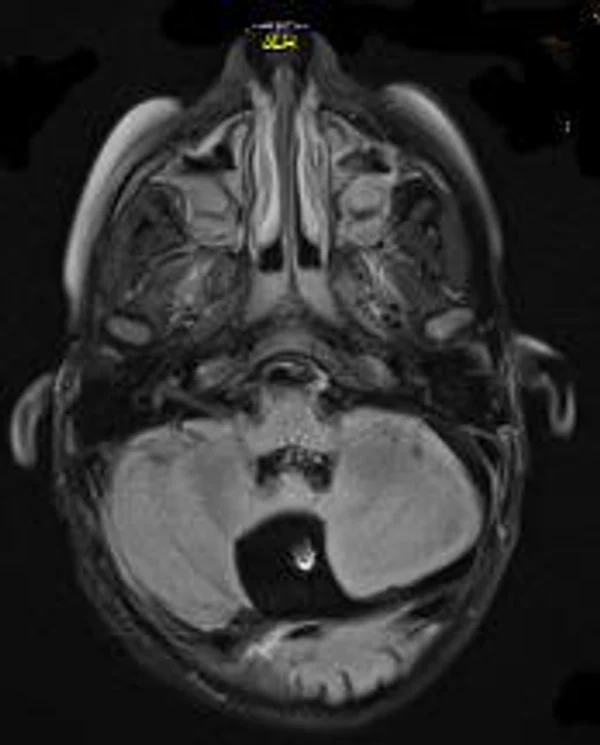

В качестве примера приведены 2 случая хирургического лечения новорожденных с врожденными опухолями головного мозга и позвоночного канала. У новорожденной девочки опухоль (хориодпапиллома) располагалась в области треугольника правого бокового желудочка (рис. 28 а, б). В возрасте 2-х недель жизни опухоль удалена. По данным МРТ головы с внутривенным введением контрастного препарата выполненной через 2 дня после операции опухоль удалена тотально (рис. 28 в). Послеоперационных осложнений не наблюдалось. У второго пациента 2-х нед. жизни врождённая опухоль (нейробластома) располагалась в позвоночном канале на уровне Th10-L3 позвонков (рис. 29 а) и распространялась в забрюшинное пространство. Клиническая картина заболевания складывалась из нижнего вялого парапареза и нарушения функции тазовых органов. Во время операции остистые отростки Th 11-L3 позвонков рассечены по средней линии. Дужки 6 данных позвонков надломлены и разведены в стороны. Опухоль располагалась экстрадурально, отделена от дорзальной поверхности дурального мешка и корешков спинно-мозговых нервов, после чего полностью удалена из позвоночного канала. Половинки дужек позвонков сведены к средней линии и сшиты между собой. Опухолевый узел в забрюшинном пространстве через 2 нед. удален онкологами. Через год после операции по данным МРТ рецидива опухоли нет (рис. 29 б). При спондилографии дефектов задней стенки и деформаций позвоночника не выявлено (рис. 29 в). Мальчик ходит, мочу и кал удерживает.